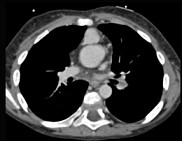

- 多项选择题患者,男性, 8岁,发绀、气促, 易感冒,彩超提示只见一个心室, CT检查如图所示,请选择正确的选项 ( )